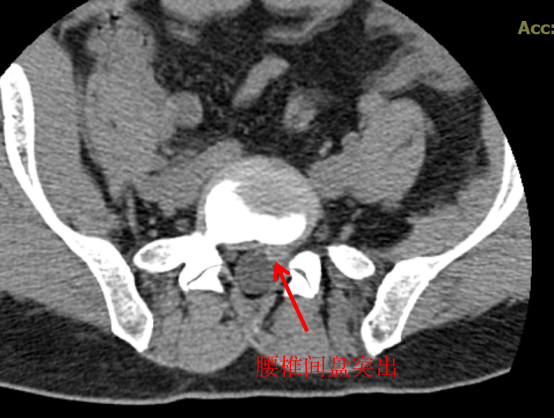

CT 檢查

CT 中文名稱叫做電子計(jì)算機(jī)斷層掃描,顧名思義就是將需要檢查的人體部位,通過(guò)電腦切成若干小層,然后把每層的圖像顯示出來(lái),所以 CT 相對(duì)于 X 光片的優(yōu)點(diǎn)就是細(xì)節(jié)顯示更清楚,一些 X 光片看不出來(lái)或看不清的隱匿性骨折,通過(guò) CT 層掃后,就能發(fā)現(xiàn)細(xì)小的骨折,這樣就很大程度上避免了漏診或誤診。

CT 也可以顯示出椎間盤(pán)有無(wú)突出,椎體內(nèi)有無(wú)骨質(zhì)破壞、椎管狹窄程度等。所以,如果懷疑一個(gè)病人是腰椎間盤(pán)突出癥,而患者又不愿意做核磁,那就應(yīng)該首選腰椎 CT。

CT 的優(yōu)點(diǎn)是可以顯示出 X 線檢查難以發(fā)現(xiàn)的隱匿性骨折,對(duì)軟組織的顯影優(yōu)于 X 光。缺點(diǎn)是價(jià)格稍貴,輻射量更大。